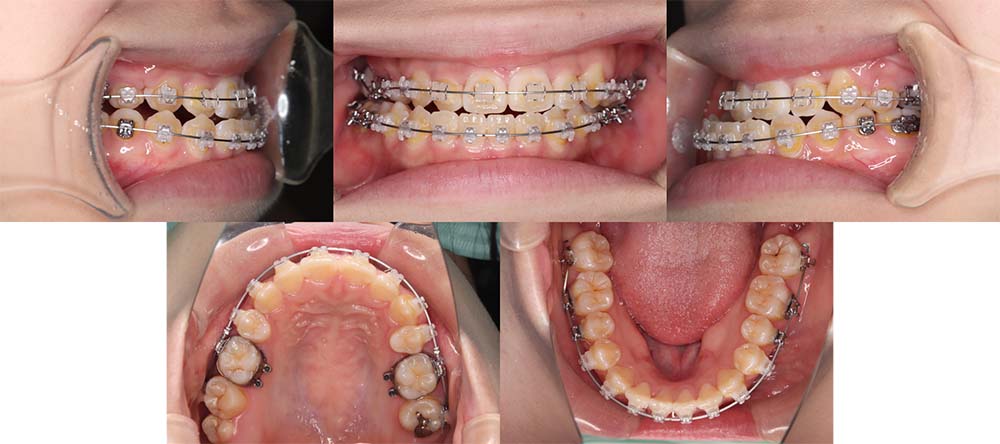

| 症例分類 | 顎変形症、叢生、側方偏移 |

| 診断名 | 下顎右側偏移を伴う上下叢生 |

| 主訴 | 歯並びがガタガタ、顎が右にずれている |

|---|---|

| 年齢 | 25歳4ヶ月 |

| 性別 | 女性 |

| 抜歯部位 | 上の左右第一小臼歯 |

| 使用装置 | 表側のワイヤー装置+外科矯正(手術を併用した治療) |

| 治療期間 | 2年1ヶ月 |

| 保定装置 | 固定式保定装置、取り外し式保定装置(8時間) |

| 費用 |

保険適応 [検査・診断等] 2万円程度 [装置装着] 5〜7万円程度 [調整料] 2,000〜7,000円程度/回 [手術前検査等] 2万円程度 [保定装置等] 4万円程度 合計18〜25万円程度 |

下顎の右側に偏移があり、骨格的にも受け口だったため、上顎両側第一小臼歯を抜去して、上下顎の手術を併用して治療を行いました。術前は前歯が反対のかみ合わせになり、初診時より咬合、顔貌は一旦悪くなります。術前矯正を1年7ヶ月した後に手術を行いました。

術後の顎間ゴムをしっかりと使用していただけたため、術後7ヶ月で治療が終了することができました。また、顎の歪みが残っていたため矯正治療終了後におとがい形成術をして、下顎の偏移を改善しました。

顎の歪みも下顎の前方感も改善することができ、上下のかみ合わせもしっかりと咬合することができました。